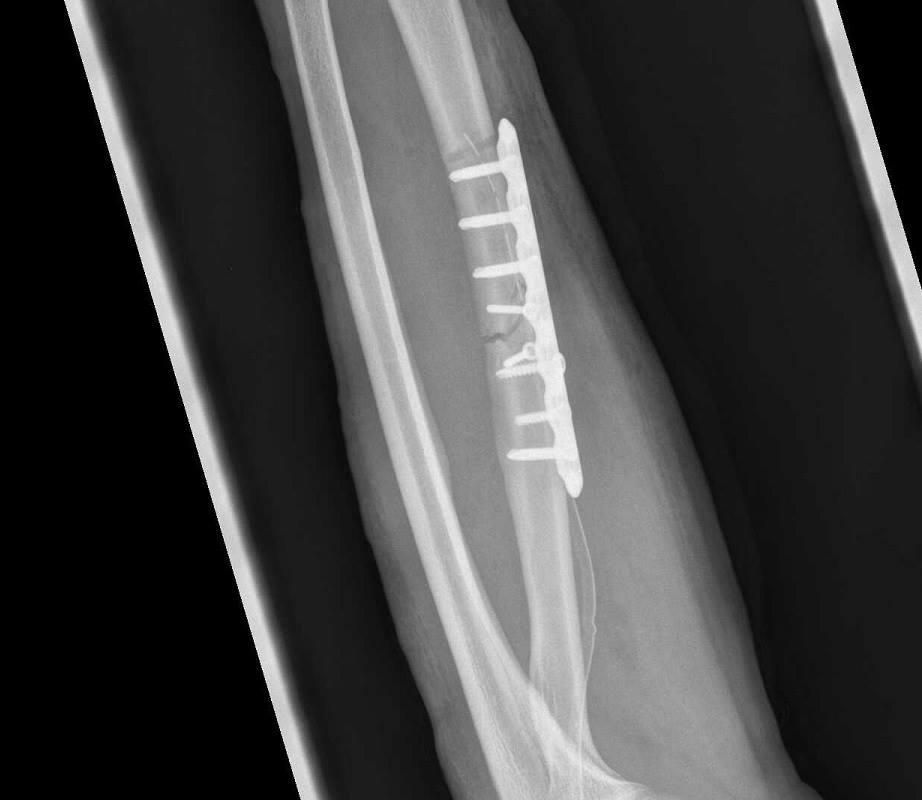

So sollte es auch 2015 weitergehen. Doch es kam anders. Bei „HCH 1200“ krachte ich nördlich von Paris, nach Einbruch der Dunkelheit, in ein Auto und brach mir den linken Arm. Ich stieg zwar fünf Wochen später bei „Paris-Brest-Paris“ erneut auf den Sattel, musste jedoch bereits nach 450 Kilometern einsehen, dass dies für mich nicht zu schaffen war. Jochen bestand seine Feuertaufe bei diesem Klassiker meisterlich und auch Olli kämpfte sich mit viel Einsatz ins Ziel.